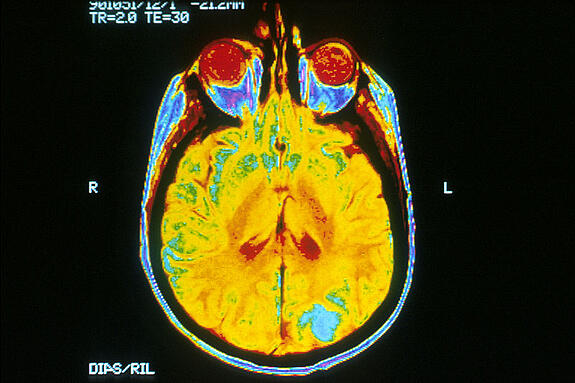

Using an advanced MRI technique, the researchers began to examine the blood flow of people who weren’t exhibiting symptoms of Alzheimer’s, but who did have a family history of the disease. Sure enough, people whose mother had Alzheimer’s displayed a reduced blood flow compared to a control group. Johnson believes this can serve as an earlier symptom for the disease, allowing doctors to take action sooner. For example, it is known that amyloid plaques build up in the brain and block neuron signals during the course of Alzheimer’s disease. With more advance notice, researchers and doctors can focus on experimenting with chemicals to break down these plaques, possibly before it’s too late.

(A human brain as shown in an MRI scan, courtesy of Wikimedia Commons)

Though it might seem like an unnecessary detail, the fact that Johnson and his team are able to determine the decreased level of blood flow simply from an MRI scan is quite remarkable in itself. Similar methods of measuring a person’s blood flow include using radiation during the scan and injecting a drug tracer for visibility. Detecting the signs of reduced blood flow using only MRI is both less expensive and less invasive. In addition, the use of brain imaging allows the research groups to test drug effectiveness with a study group of just two hundred people- as opposed to the 1500 or 2000 needed for conclusive data in similar methods.